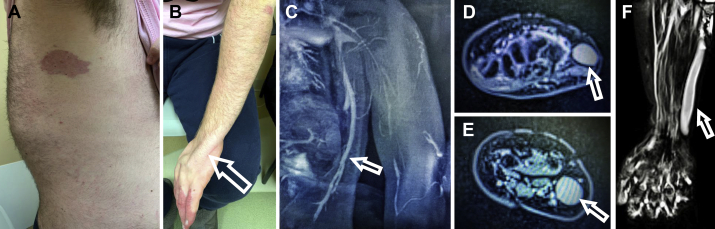

A 17-year-old boy presented with chronic pain and swelling of the left upper extremity in the setting of spinal scoliosis, lipomatous overgrowth of the left posterolateral upper trunk, and multifocal port-wine stains of the left hand and trunk (Fig 1, A and B). Magnetic resonance and duplex ultrasound imaging revealed thoracic phlebectasia draining the anomalous veins of the left lateral chest wall into the left axillary vein (Fig 1, C) as well as an enlarged incompetent anomalous marginal vein extending from the dorsum of the left hand to the axilla, draining into an intact deep system (Fig 1, D-F). A clinical diagnosis of CLOVES syndrome was made. Treatment of these incompetent, anomalous venous structures was warranted to address symptoms, to prevent hematologic derangements, and to minimize risk of thromboembolic events.1 The patient consented to publication of this report.

Fig 1.

A, Congenital lipomatous overgrowth, vascular malformations, epidermal nevi, and skeletal deformities (CLOVES) syndrome with its characteristic port-wine stain. B, Subdermal, ulnar location of an incompetent anomalous vein in the left upper extremity (arrow). C, Magnetic resonance venography of thoracic phlebectasia of CLOVES syndrome (arrow). D-F, Magnetic resonance venography of the incompetent anomalous vein at the level of (D) wrist and (E) forearm, (F) extending from the dorsum of the left hand along the ulnar aspect (arrow).